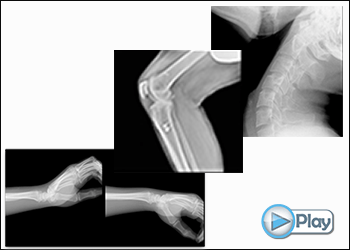

Shimadzu Corporation, in collaboration with and Konica Minolta, Inc. have developed Dynamic Digital Radiology (DDR) incorporating Konica Minolta’s new advanced image processing and Shimadzu’s RADspeed Pro style edition radiographic imaging system. DDR is an enhanced X-ray technology that provides a series of low dose individual digital images acquired at high speed. The resulting cine loop enables clinicians to observe the dynamic motion of anatomical structures over time, enhancing diagnostic capabilities. The motion series can be analysed and quantified with the DDR advanced image processing capability.

DDR provides endless applications including — thoracic and orthopedic — chest, diaphragm, lung, spine, shoulder, wrist, ankle & knee. DDR is for initial assessment, before surgery and follow-up.

- • DDR for Orthopaedics: Detecting musculoskeletal injury by movement